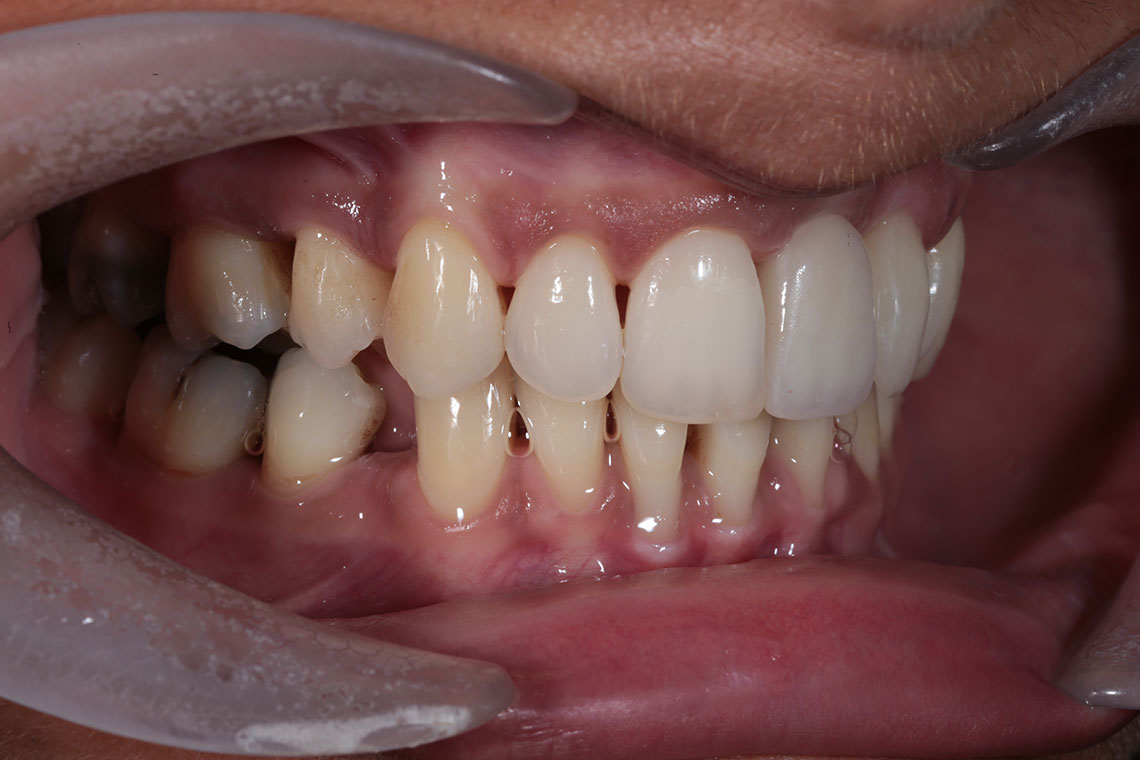

This lovely lady attended with very low confidence due to her teeth and smile. Gum disease and trauma had led to the teeth drifting. One of her front teeth was so loose that it needed to be replaced. We started by providing intensive treatment with our dental hygienist to treat the gum disease. Following this Invisalign® braces were used to align the teeth and the teeth were whitened. A dental implant was then placed to replace the loose front tooth and composite bonding was performed to the adjacent front tooth. The change in the patient’s confidence as a result of this work was breathtaking.